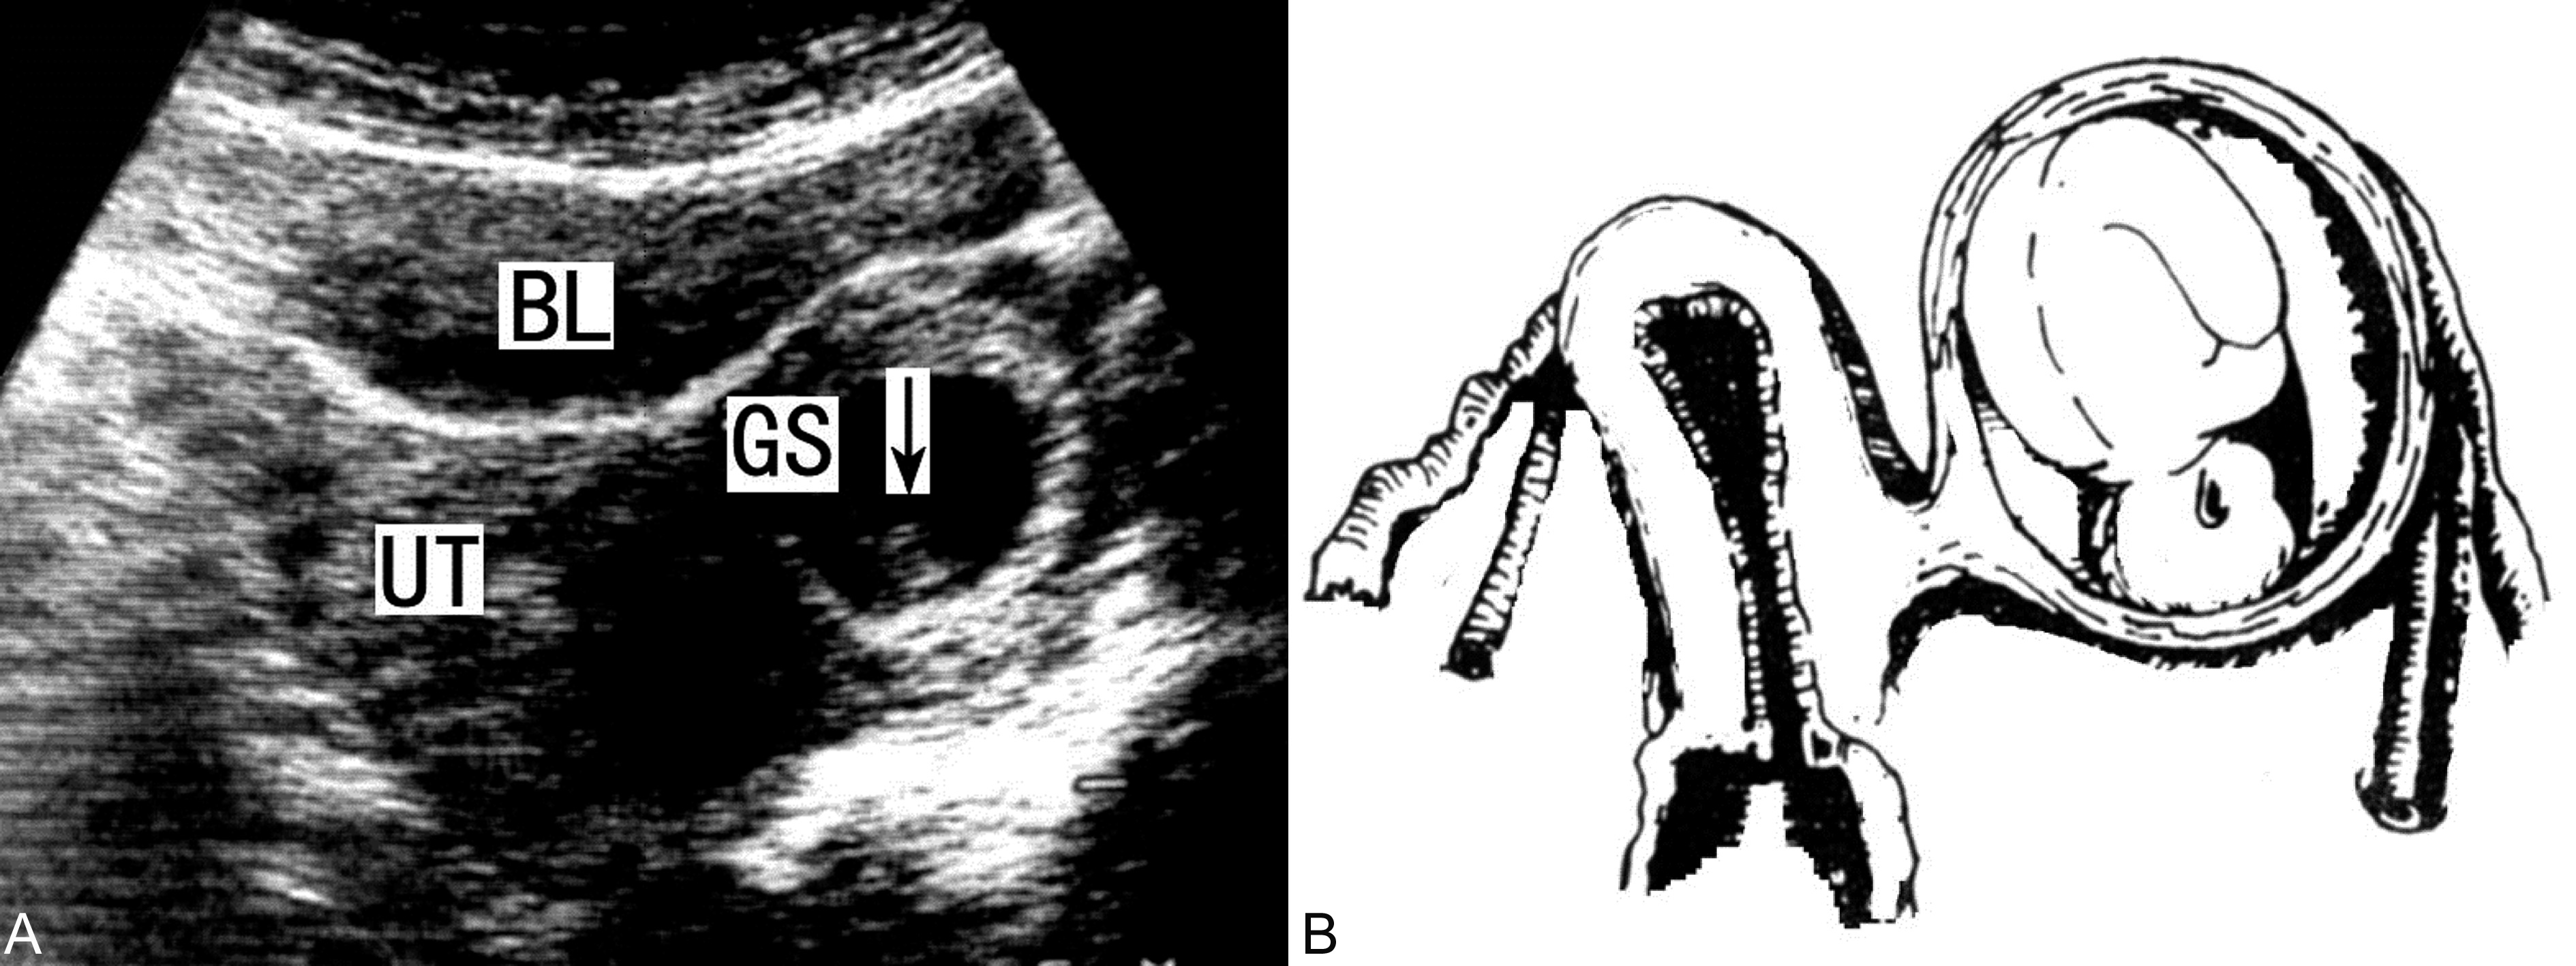

在妊娠早期,残角子宫未破裂前,超声显像检查可以发现一个相对较小的子宫和宫旁的异常回声,与输卵管妊娠相似,可以显示单角子宫内假孕囊回声和对侧形态正常的妊娠囊和胚胎回声,仔细检查可以在妊娠囊周围显示较厚的肌肉组织,相对独立(图2),与对侧子宫有稍强的间隔回声,并且不能发现同侧的子宫颈而与双子宫不同,同侧卵巢可以显示且回声基本正常。结合临床检查资料可以做出子宫残角妊娠的诊断。此点也可能是子宫残角妊娠与输卵管妊娠和双角子宫妊娠的鉴别要点。

图2子宫残角妊娠声象图(A:左侧单角子宫显示孕囊GS及胚胎;B及示意图)

子宫残角妊娠破裂后可以显示与输卵管妊娠相似的回声图像,在子宫旁显示由妊娠产物和出血形成的团块状回声,体积多数较大,出血量常较多,但很少能够显示残存的肌壁回声。如果能够发现肌壁回声,则应首先考虑为子宫残角妊娠破裂。但多数情况下超声显像检查很难将破裂的子宫残角妊娠与破裂的输卵管妊娠鉴别。